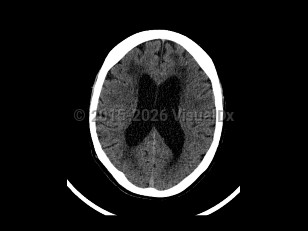

Normal pressure hydrocephalus (NPH) is a common neurologic disorder resulting in slowly progressive gait abnormalities, cognitive deterioration, and urinary incontinence.

The incidence of NPH increases with advancing age, and most patients are over the age of 60. There is no difference in incidence between men and women. NPH has an estimated incidence of 1-5 cases per 100 000 people per year. Its prevalence is reported to be less than 1% in persons under the age of 65, and up to 3% for persons aged 65 or older. Among individuals with dementia, the incidence of NPH is thought to be between 2% and 6%.

Approximately 40%-75% of patients with suspected NPH are subsequently found to have other comorbid neurodegenerative diseases such as Alzheimer disease. NPH patients with other comorbid neurodegenerative conditions are thought to have a poorer response to CSF shunting.